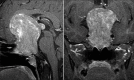

Case description: The authors report the case of a Brazilian 27-year-old man who presented with progressive vision loss during the last 4 years and serious bilateral keratoconus. We also review the epidemiological, clinical, radiological, pathological, and treatment features of the 12 reported cases. The patient developed left amaurosis and right temporal hemianopsia after undergoing bilateral corneal transplantation, which was detected during campimetry testing, and subsequently underwent magnetic resonance imaging, which revealed a huge hypophyseal tumor. Endocrinological evaluation revealed complete loss of pituitary function. The patient was referred to our department and underwent a two-step surgery (using transsphenoidal approach and cranio-orbital zygomatic approach) based on the diagnosis of an extraventricular central nervous system neurocytoma. Tumor removal was successful, and the patient was discharged at 3 weeks after admission to our department.